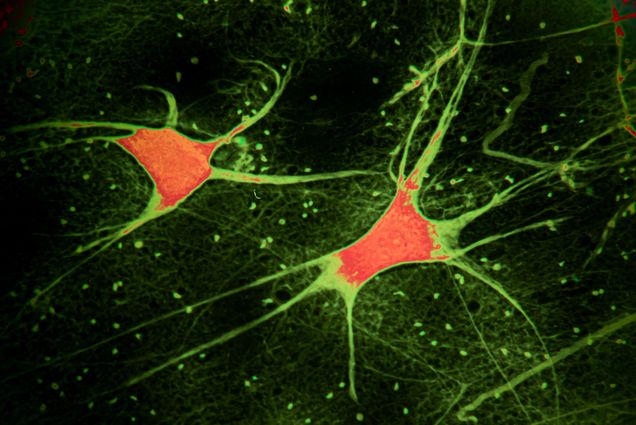

Neuroscience

How Sleep Is Impacted by Brain Circuitry and Aging